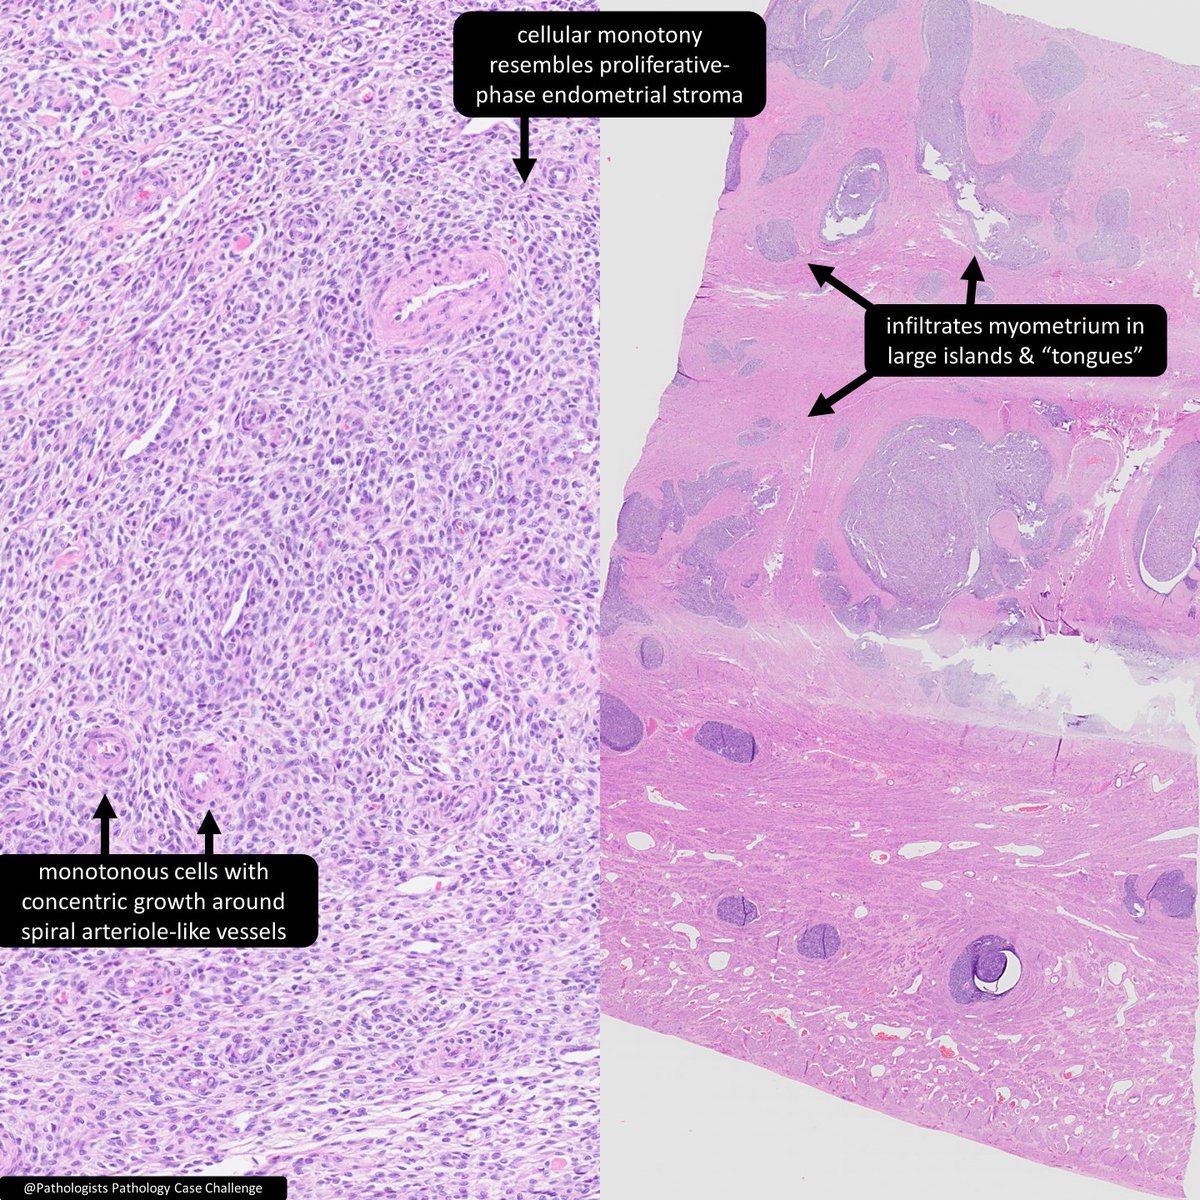

Endometrial stromal ___ a) nodule b) sarcoma 🔬@Pathologists https://t.co/1z7GBOsejY #GYNPath #PathTwitter #Pathology #BSTPath